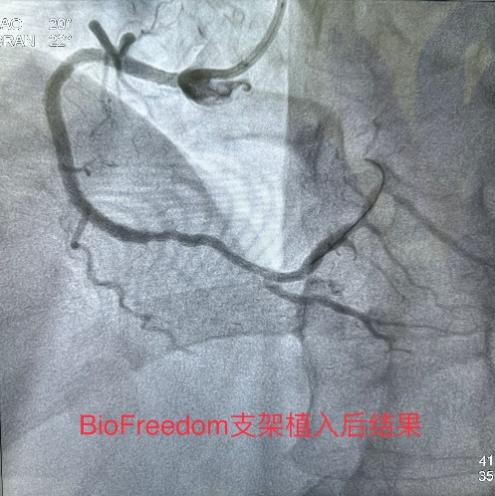

3月8日经过充分的术前准备,雷新军教授带领景林德博士和蔡安琪医生按照预定方案为患者实施了手术。冠脉造影示:RCA 2段慢性闭塞合并重度钙化,闭塞段长约30 mm,同向桥侧支供血使其远段显影(图3a);前降支散在斑块伴钙化,狭窄约25%-50%,并通过间隔支侧支循环向右冠逆向供血(图3b);回旋支11段狭窄约75%(图3c)。决定干预右冠:指引导管到位后在Guidezilla的支撑下,经Corsair微导管仔细操控GAIA 3rd穿过闭塞段进入远端血管真腔(图3d,e);然后通过微导管交换成旋磨导丝,使用1.5 mm Burr进行冠脉内斑块旋磨并抛光(图3f),造影见右冠恢复TIMI 3级前向血流,但2段残余狭窄最重处仍达90%(图3g);遂经导丝送入3.0*12 mm“Shockwave”冲击波球囊分段进行血管内碎石术:首先将压力充盈至4 atm后开始释放脉冲,松解钙化斑块,然后再将充盈压升至6 atm维持10秒,对靶病变进行低压球囊扩张成形(图3h);再次造影见右冠2段局限性夹层,闭塞段残余狭窄<10%(图3i),效果非常满意,遂由远及近衔接植入BioFreedom支架(图3j),历时约1小时手术成功,病人安返病房。

图3 经皮冠脉介入治疗

冠脉斑块旋磨术联合冲击波球囊治疗是目前临床实践中征服重度冠脉钙化病变的优化组合技术,不仅可以提高手术成功率,减少围手术期并发症,而且还极有可能改善患者远期获益,值得在临床上推广应用。该技术的应用使得青海省人民医院成为全国率先开展该技术的医院之一,也标志着青海省人民医院心内科冠脉介入诊疗水平再上新台阶(图4)。